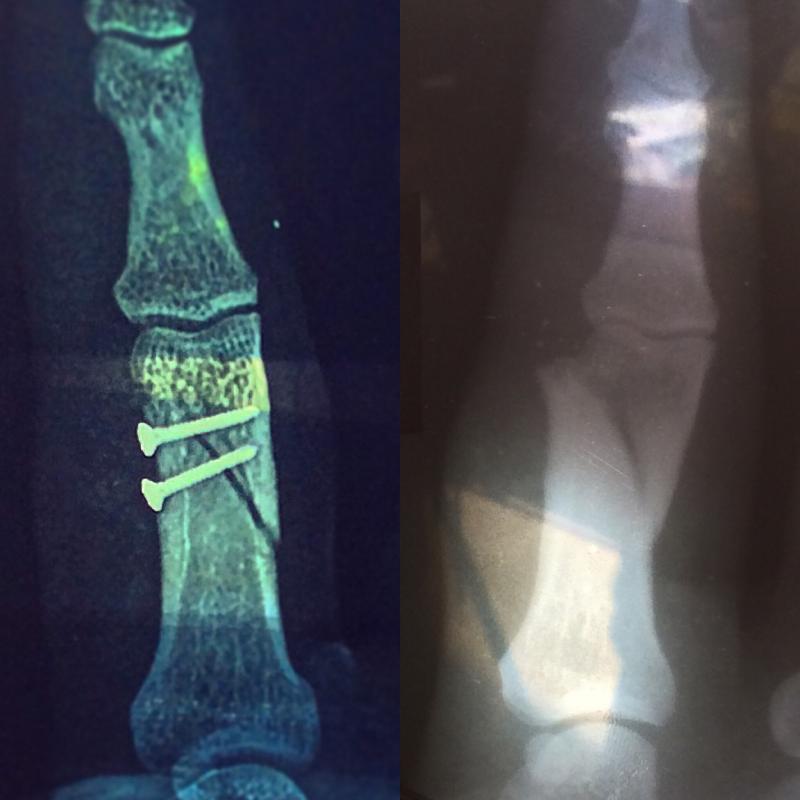

Главная > Железки > Поломки и падения

палец?=)))

Ну да -)

Это типо операция такая? Саморезы загнать туда?!

Да

Саморезы сам вкручивал?) А если серьезно - выздоровления

ну да, смещение некислое было до операции